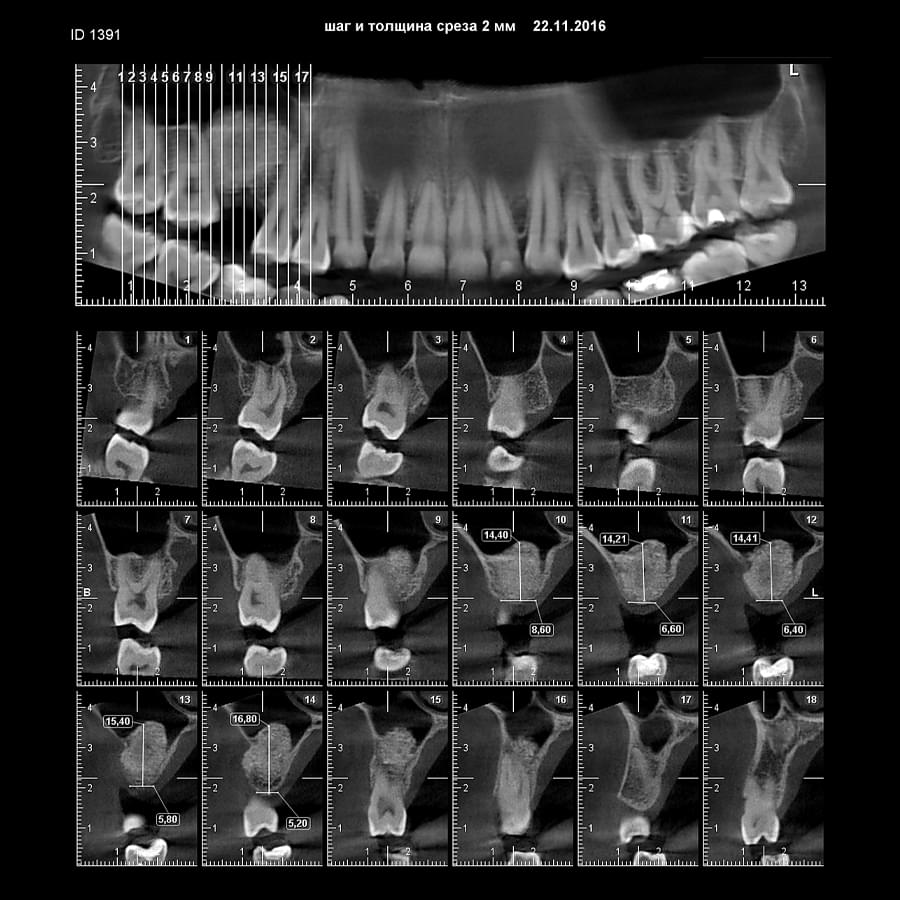

Комп'ютерна томографія

Щелепно-лицева діагностика

Ми використовуємо найсучасніше обладнання відомого виробника PLANMECA, що дозволяє отримувати високоякісні зображення за короткий час. Крім того, ми маємо власний сервер, на якому створюємо окрему скриньку для кожного лікаря, що забезпечує максимальну зручність та ефективність роботи.